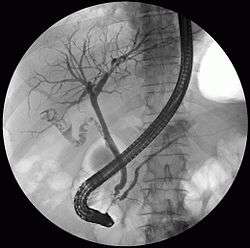

| MRCP image of two stones in the distal common bile duct | |

The diagnosis of choledocholithiasis is suggested when the liver function blood test shows an elevation in bilirubin and serum transaminases. Other indicators include raised indicators of ampulla of vater (pancreatic duct obstruction) such as lipases and amylases. In prolonged cases the INR may change due to a decrease in vitamin K absorption. (It is the decreased bile flow which reduces fat breakdown and therefore absorption of fat soluble vitamins). The diagnosis is confirmed with either an MRCP (magnetic resonance cholangiopancreatography), an ERCP, or an intraoperative cholangiogram. If the patient must have the gallbladder removed for gallstones, the surgeon may choose to proceed with the surgery, and obtain a cholangiogram during the surgery. If the cholangiogram shows a stone in the bile duct, the surgeon may attempt to treat the problem by flushing the stone into the intestine or retrieve the stone back through the cystic duct.

On a different pathway, the physician may choose to proceed with ERCP before surgery. The benefit of ERCP is that it can be utilized not just to diagnose, but also to treat the problem. During ERCP the endoscopist may surgically widen the opening into the bile duct and remove the stone through that opening. ERCP, however, is an invasive procedure and has its own potential complications. Thus, if the suspicion is low, the physician may choose to confirm the diagnosis with MRCP, a non-invasive imaging technique, before proceeding with ERCP or surgery.